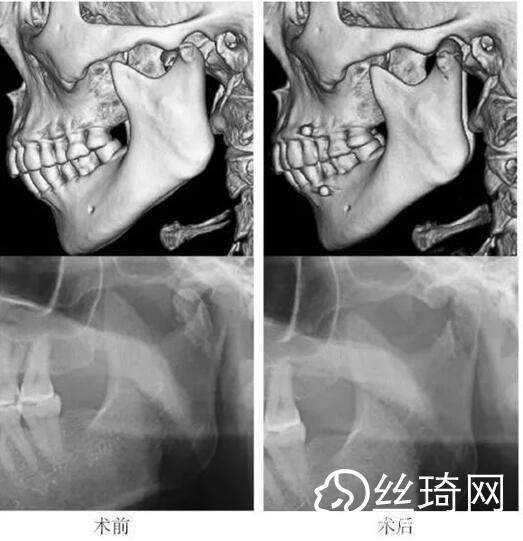

在106側(cè)中,髁突高位矢狀骨折46側(cè),中位髁頸骨折26側(cè),低位髁頸下骨折34側(cè)。髁突高位矢狀骨折及中位髁頸骨折均經(jīng)耳屏前徑路復(fù)位;34側(cè)低位髁頸下骨折中,經(jīng)耳屏前徑路復(fù)位13側(cè),頜下徑路復(fù)位19側(cè),頜后徑路復(fù)位1側(cè),穿腮腺徑路復(fù)位1側(cè)。髁突高位矢狀骨折復(fù)位后以1~2枚可吸收長螺釘固定(圖1)[3],采用的可吸收內(nèi)固定系統(tǒng)為BioSorb(ConMed Linvatec,芬蘭)、Inion OTPS(Inion,芬蘭);規(guī)格:直徑2 mm,長度15~20 mm。中位髁頸骨折及低位髁頸下骨折多以2塊可吸收板固定(圖2)[3],個別病例以1塊或3塊可吸收板固定,采用的可吸收內(nèi)固定系統(tǒng)為BioSorb(ConMed Linvatec,芬蘭)、Grand Fix(Gunze,日本)、Inion OTPS(Inion,芬蘭);規(guī)格:直4孔板,孔徑 mm或2.5 mm,長度21~35 mm,螺釘直徑 mm或2.5 mm,長度7~10 mm??晌蔗敯宓氖中g(shù)操作采用專用器械工具盒,并遵照廠家操作指引進行。

82例髁突骨折患者,術(shù)后隨訪6個月至3年,平均年。所有患者術(shù)后未訴明X不適,面型基本對稱,面部肌肉運動正常,咬合對位良好,開口度~4.2 cm,平均(±)cm。3例患者開口型輕度偏斜,均為髁突高位骨折,其中2例為粉碎性骨折行骨折碎片摘除,1例為矢狀骨折,以可吸收螺釘固定后,創(chuàng)口感染,隨后行局部清創(chuàng)并取出髁突骨折片及可吸收螺釘,創(chuàng)口愈合良好。96側(cè)髁突骨折中,2例髁頸下骨折術(shù)后復(fù)查CT顯示輕度移位,但患者無功能障礙,持續(xù)觀察,未做特殊處理。其他患者未見明X排斥反應(yīng)及并發(fā)癥。

本組病例中,絕大多數(shù)髁頸、髁頸下骨折均經(jīng)耳屏前或頜下切口進行復(fù)位固定,均獲得了良好的復(fù)位固定性及療。有2例患者輕度移位,可能與過早承重及可吸收材料的強度較弱有關(guān)。